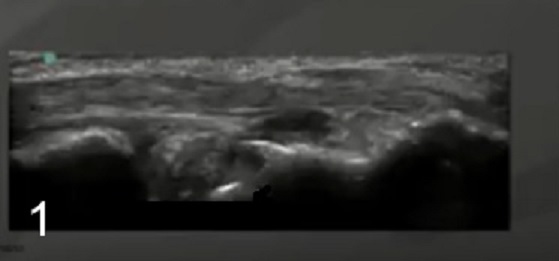

Foot & Ankle Peroneal Tendon 1 Image